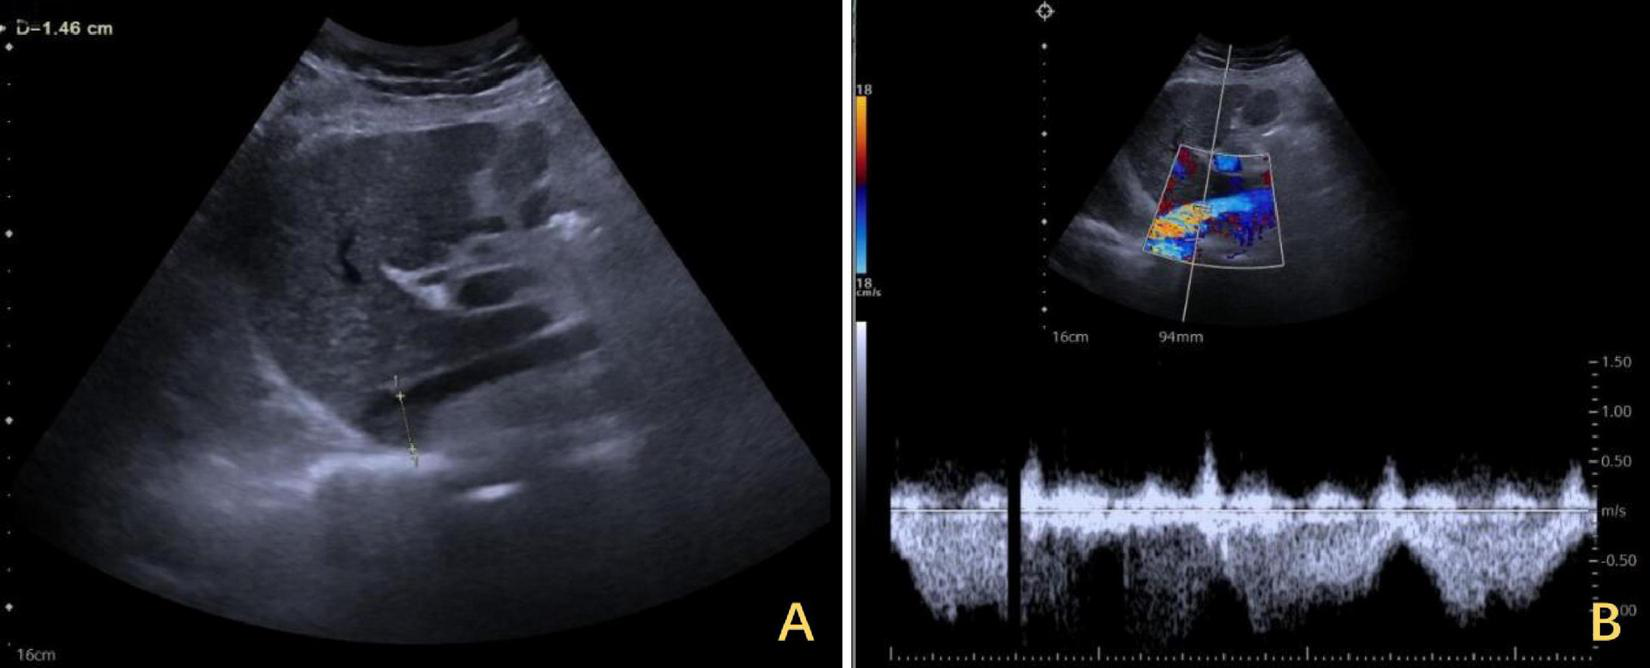

FIGURE 2

Ultrasound findings of IVC stenosis with outflow obstruction. (A) The IVC was approximately 0.33 cm wide, with its lower segment expanding to 2.8 cm. The arrows highlighted in yellow indicate stenosis. (C) The flow increased to 0.134 m per second. (B) After the release of the outflow tract obstruction after DP, the diameter of the IVC increased to 1.2 cm. (D) The flow rate returned to normal. IVC, inferior vena cava; DP, diaphragmatic plication.

The right diaphragm dropped to almost the same level as the left diaphragm on the third day after DP (Figure 4B). The patency of the IVC stenosis was restored with by increasing the internal diameter to 1.2 cm (Figure 2B). And the flow rate returned to normal (Figure 2D). The patient’s blood ammonia level decreased to 66.4 μmol/L. She had a thoracic close drainage removed on the third postoperative day, had no postoperative complications, and was discharged on the fourth postoperative day. At 1 year postoperative follow-up, ultrasonographic evaluation of IVC revealed a maximum diameter of 1.46 cm, with a mean flow velocity of 0.5 m per second and peak velocity of approximately 1 m per second (Figure 7). Serial blood ammonia monitoring demonstrated persistently normal levels throughout the follow-up period (Figure 8).

FIGURE 7

One-year follow-up ultrasound of the IVC after DP. (A) The maximum diameter of the IVC was 1.46 cm at its widest segment. (B) The IVC exhibited a mean flow velocity of 0.5 m per second, with a peak velocity of approximately 1 m per second. IVC, inferior vena cava; DP, diaphragmatic plication.